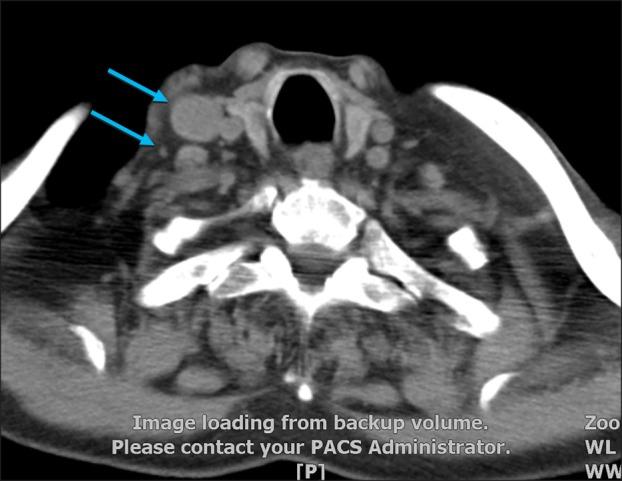

Indeterminate dendritic cell tumor (IDCT) is a proliferation of CD1a+, S100+ and langerin- histiocytes with a generally benign course. Here, we describe a case of a 90-year-old male who developed skin lesions on his scalp mimicking angiosarcoma and lymphadenopathy. He died six months after the onset of skin lesions despite of months' radiotherapy. Pathological examination ruled out scalp angiosarcoma and showed a high Ki-67 index. The appearance of skin lesions and lymphadenopathy led to challenges in diagnosis and the development of a treatment plan.

未定型树突状细胞肿瘤(IDCT)是一种CD1a+、S100+和郎格罕蛋白阴性的组织细胞增殖性疾病,通常病程呈良性。在此,我们描述一例90岁男性病例,其头皮出现类似血管肉瘤的皮肤病变及淋巴结病。尽管进行了数月的放疗,但他在皮肤病变出现6个月后死亡。病理检查排除了头皮血管肉瘤,且显示Ki-67指数较高。皮肤病变和淋巴结病的表现给诊断及治疗方案的制定带来了挑战。